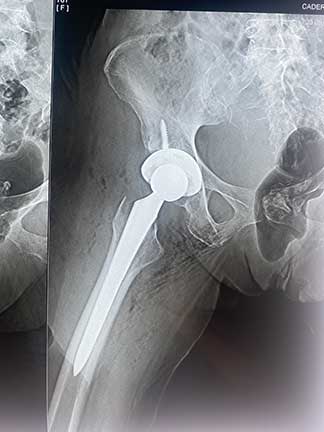

Prótesis de cadera

Es también conocida como reemplazo de cadera, la cual consiste en la sustitución de la articulación dañada o un implante de metal, cerámica o plástico que realiza la función de la articulación, mejorando el dolor.

¿Por qué se realiza?

Las indicaciones más comunes son la artrosis o desgaste de cadera en adultos mayores, otras indicaciones son las fracturas de cadera, el daño crónico o infección, artritis reumatoide, secuelas de enfermedades de la cadera o traumatismos, las cuales se presentan en adultos jóvenes y adultos mayores.

Cuidados después de la intervención

El paciente puede caminar desde el mismo día de la cirugía, se da de alta a su domicilio a las 24 horas y puede realizar actividades cotidianas en casa de forma autónoma desde la primera semana. La recuperación parte en un 80% de la función de la cadera en el primer mes, 90% de la función en el segundo mes y 92% - 98% de la función en el tercer mes.

Resultados esperados

Eliminar el dolor en la zona afectada, mejorar la función como es fuerza muscular, movimiento, estbilidad y biomecánica, logrando mejorar la calidad de vida del paciente.